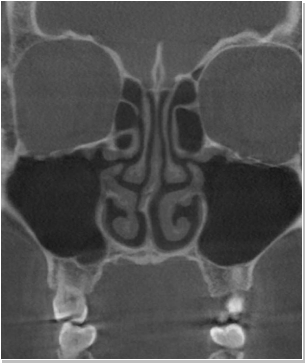

코재수술 CT 전후사진

비염

비중격만곡증

축농증